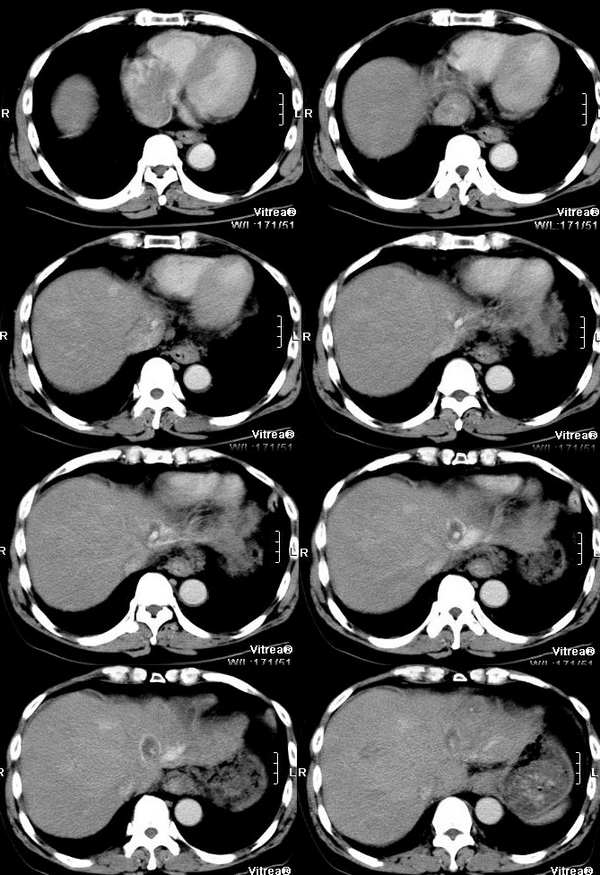

男性,58岁,肝硬化数年,近几个月出现黄疸,腹胀,食欲下降,尤其双下肢浮肿明显。超声提示肝脏多个结节。ct三期扫描图像如下:

平衡期:

肝静脉:在动脉期的第一张图片上就可以看到右心房的充盈缺损和下腔静脉近心段的明显增粗,增粗的下腔静脉内部可以见到点状、条状的强化血管影,这些强化的血管影是什么来源?这些高密度影蜿蜒曲折,和主动脉同时显影,所以只能考虑为主动脉的分支血管之一。到门脉期和平衡期,右心房的充盈缺损更加明显了,肝静脉和下腔静脉的强化非常微弱,肝段下腔静脉的管腔十分狭窄,但肝外段的下腔静脉明显的饱满,这是由于右心房的充盈缺损和下腔静脉近心段的栓子梗阻造成的。在动脉期肝左叶有一条横行血管也非常引人注目,考虑为肝左静脉的可能,但其汇入腔静脉端呈一盲端,估计终止于栓子部位,该血管的过早显影提示存在动静脉分流,从病因上来说以原发性肝癌最为常见。在临床上,该患者有双下肢明显的浮肿,要用下腔静脉的梗阻来解释。

肝实质:该患者既有门静脉供血的下降又有肝静脉的回流异常,形成了比较复杂的强化效果。由于门静脉为入肝血管,它的梗阻造成肝脏的强化幅度明显下降,但在延迟扫描时,其引流范围内的血液会经过侧枝循环逐渐进入,所以其密度会缓慢地上升。另外又由于肝静脉的回流异常,会引起布查氏综合征的密度改变,造成肝实质密度不均匀。

肿瘤:由于肝脏本身存在血液循环的异常,所以肿瘤的血供也会受到影响。该患者在动脉期肝左叶见到明显扩张的肝动脉分支和肝左静脉的早期显影,强烈提示左叶病变。尽管没有见到明显的动脉期肿瘤强化,但仔细观察还是有动脉供血病变的,不过密度较淡,边缘模糊;在平衡期,左叶肿瘤露出其真面目,和肝脏实质相比呈低密度。由于患者有多年肝硬化病史和存在动静脉分流和静脉栓子,综合考虑还是应该首先考虑为原发性肝癌。另外腔静脉内栓子动脉期明显动脉供血,也是肝癌癌栓的特征,这一点和hejie的意见不同。

综上所述,我考虑为肝癌并门静脉和下腔静脉近心段以及右房癌栓形成。